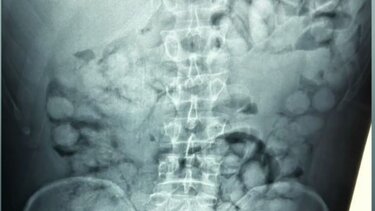

Στις ακτινογραφίες που έδωσε στη δημοσιότητα η Ελληνική Αστυνομία, διακρίνονται οι συσκευασίες που είχε καταπιεί με τους γιατρούς να εντοπίζουν 100 κάψουλες των 11 γραμμαρίων η καθεμία.

Η συγκεκριμένη μέθοδος διακίνησης ναρκωτικών είναι εξαιρετικά επικίνδυνη, αφού αν άνοιγε στο στομάχι του έστω και μία συσκευασία, σε λίγα λεπτά θα είχε πεθάνει. Σύμφωνα με τις πρώτες πληροφορίες, η συνολική ποσότητα κοκαΐνης που εντοπίστηκε ξεπερνάει το ένα κιλό. Η έρευνα των αρχών συνεχίζεται για τον εντοπισμό και άλλων εμπλεκομένων στην υπόθεση.